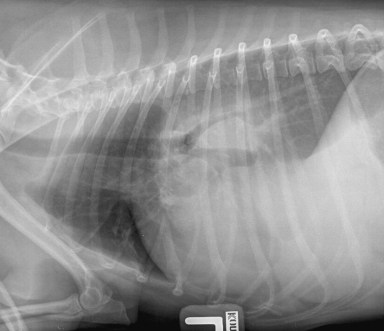

Signalement: chien croisé berger, mâle castré, 10 ans.

Histoire clinique: toux chronique et perte de poids